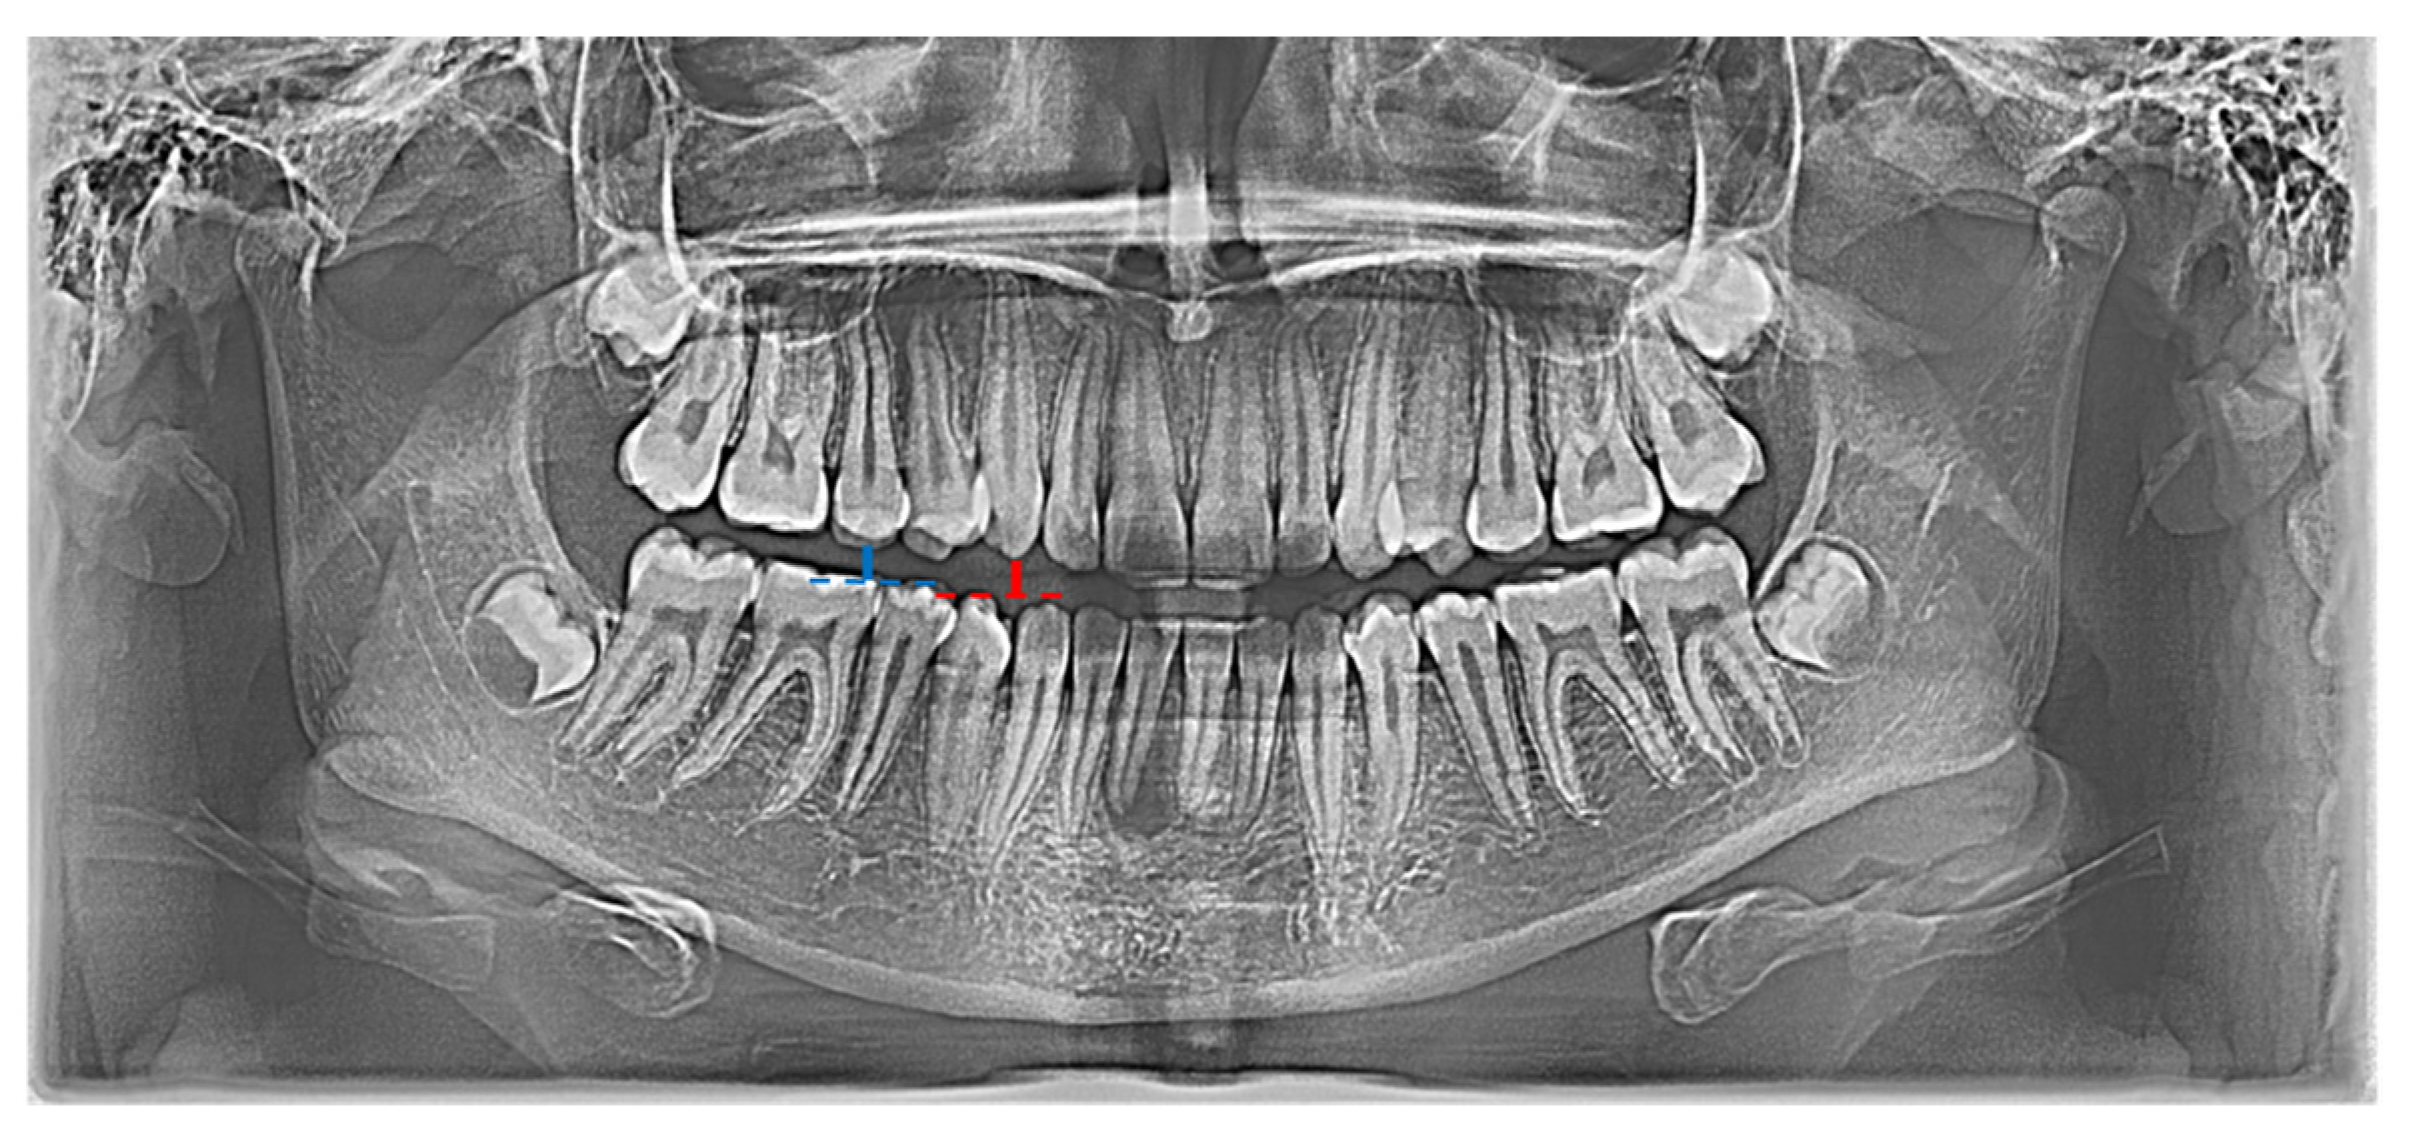

In the conducted research, a set of 21 indicators was used, estimated by Zaborowicz [37]. These indicators were selected to capture most of information about the condition of teeth of children and adolescents. As pantomographic images are not made on a fixed scale, all indicators are calculated as proportions of individual geometric distances, lengths of selected teeth, etc. Please refer to the latest work by Zaborowicz et al. [29], where all the details and descriptions of the indicators can be found. In this work, in order to avoid repetition, only the most important description of the methodology for calculating empirical data is given. Pantomographic photos taken with the Duerr Dental VistaPano S Ceph apparatus were used for the tests. This camera records digital images in the DI-COM 3.0 format, which is supported by the specialized software DBSWIN [38] used for the analysis of 16-bit grayscale, i.e., images dedicated to medicine, including oncology, ophthalmology, cardiology, surgery and dentistry [38]. To collect all indices, i.e., tooth and bone parameters the free, open-source software ImageJ 1.52a [39] was used. Figure 1 and Figure 2 show sample photos and measurements.

Figure 2. Graphical representation of selected indicators: X01 (red |C13C43|; blue |C15C45|), X02 (red |C13C43|; green |C16C46|), X03 (red |C13C43|; orange |C17C47|).